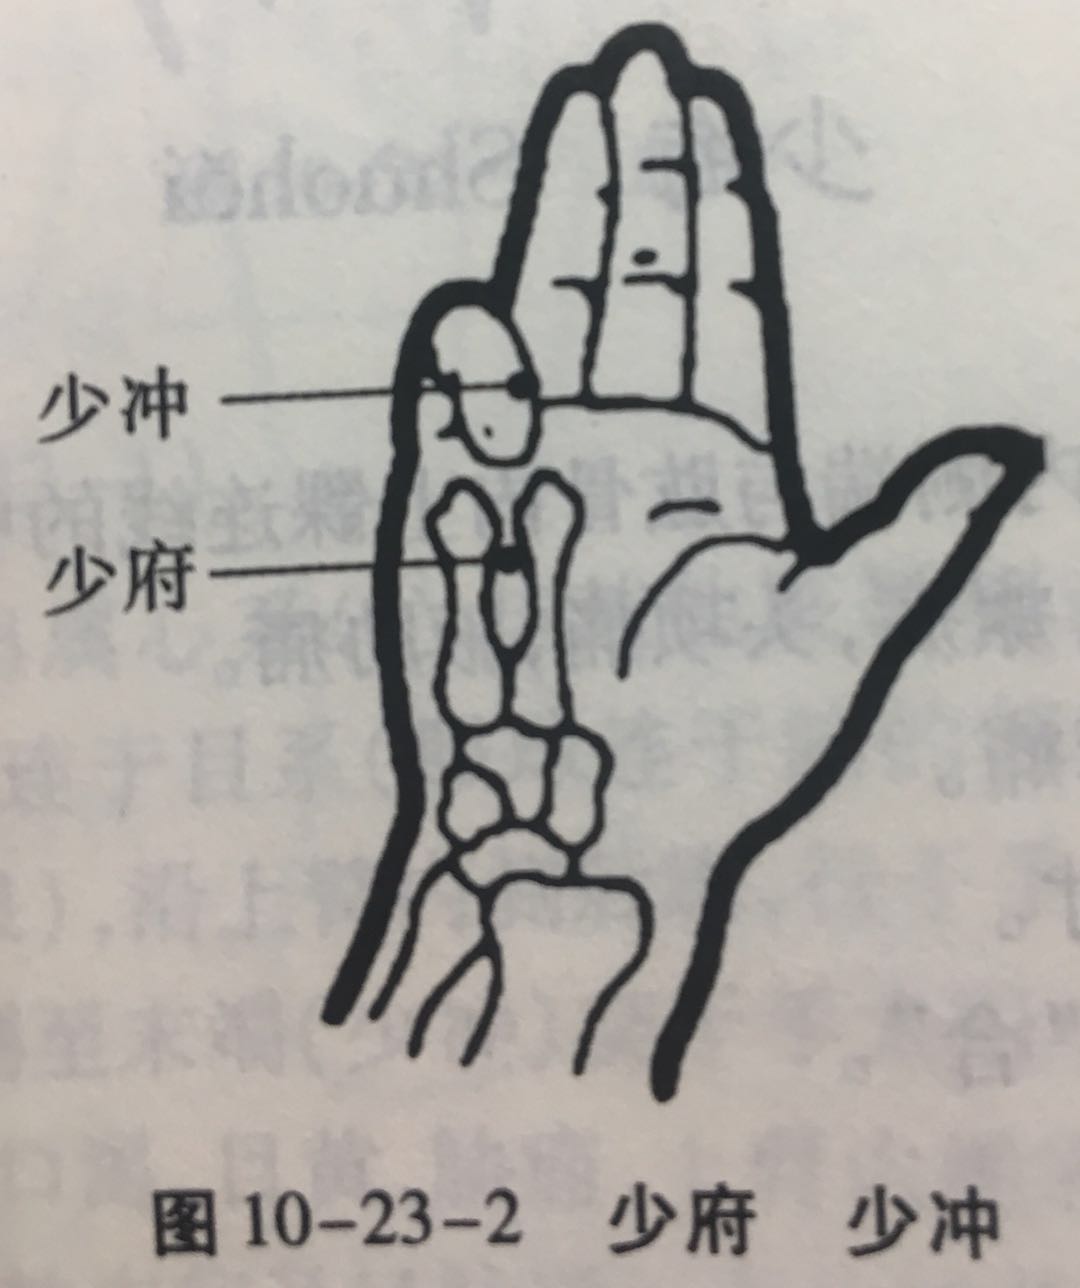

少府

【定位】 在手掌面,第 4、5 掌骨之间,握拳时,当小指与无名指指端之间。

少冲

【定位】 在小指末节桡侧,距指甲角 0.1 寸(图 10-23-2)。